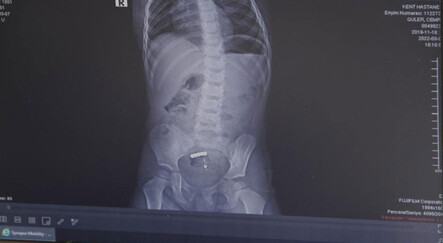

Hasta acil geldiğinde direkt detaylı değerlendirme yapılması gerektiğini belirten Genel Cerrahi Uzmanı Op. Dr. A. Murat Koca, “Daha sonrasında tetkikler yapılır. Kalp grafisi ve kan tetkiki ciddi bir kalp sorunu ekarte etmekte gerekebilir. Akciğer filmi, göğüs boşluğunda olan bir sorun varsa yansıyan şikayetler açısından önemlidir. Batın bilgisayarlı tomografi, iç organlar detaylı değerlendirmesi için gerekebilir. Tomografi pankreas, dalak, aorta ve diğer organlar hakkında bilgi verir. Tabi kan ve idrar tetkikleri yapılması da gerekir.” ifadelerini kullandı.